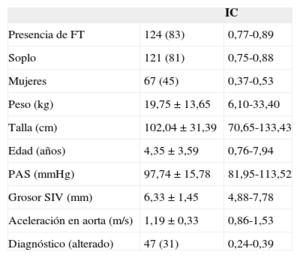

Resultados de estudios clínicosResultados del estudio clínico en la población pediátricaLos resultados del estudio clínico en la población pediátrica mostraron soplo cardiaco en el 81% (IC95%, 0,75-0,88) de los pacientes que acudieron a la consulta de cardiología, y se encontró FT en el 83% de los pacientes atendidos (tabla 3). De los FT hallados, en el 75% había un FT; en el 24%, dos y únicamente en el 1%, tres o más. Su localización era preferentemente en la zona media (67%), ápex cardiaco (22%) y tercio superior (11%). En los resultados no se observaron diferencias entre presencia y ausencia de FT en relación con edad, sexo, peso, talla, presión arterial, grosor del septo interventricular o presencia de enfermedad cardiaca, que definimos como alteración electrocardiográfica o morfológica mediante ecocardiografía. En cambio, sí vimos relación significativa del FT con la presencia de soplo inocente infantil y con una menor aceleración en la aorta descendente (p < 0,05) (tabla 4).

Descripción del estudio poblacional pediátrico

| IC | ||

|---|---|---|

| Presencia de FT | 124 (83) | 0,77-0,89 |

| Soplo | 121 (81) | 0,75-0,88 |

| Mujeres | 67 (45) | 0,37-0,53 |

| Peso (kg) | 19,75 ± 13,65 | 6,10-33,40 |

| Talla (cm) | 102,04 ± 31,39 | 70,65-133,43 |

| Edad (años) | 4,35 ± 3,59 | 0,76-7,94 |

| PAS (mmHg) | 97,74 ± 15,78 | 81,95-113,52 |

| Grosor SIV (mm) | 6,33 ± 1,45 | 4,88-7,78 |

| Aceleración en aorta (m/s) | 1,19 ± 0,33 | 0,86-1,53 |

| Diagnóstico (alterado) | 47 (31) | 0,24-0,39 |

FT: falso tendón del ventrículo izquierdo; IC: intervalo de confianza; PAS: presión arterial sistólica; SIV: septo interventricular.

Los valores expresan n (%) o media ± desviación estándar.

El estudio poblacional pediátrico halló FT visualizado por ecografía en un 83% de los pacientes, que es la mayor frecuencia de FT encontrada por ecografía de los estudios publicados hasta el momento. Ello se explica por la mejora técnica de los ecógrafos, además del enfoque del estudio encaminado a la visualización de dicha estructura. La explicación a no encontrar el 100% de los FT (como en los estudios de disección) es doble; por un lado, en ocasiones los FT son de pequeño grosor y pueden pasar inadvertidos; por otro, la visualización de FT situados en el ápex puede no ser posible, ya que es una región de difícil exploración ecocardiográfica donde se sitúan la mayoría de los FT observados en la disección.

Como en algunos estudios previos16–18, se demuestra relación estadísticamente significativa entre la presencia del FT visualizado en ecocardiografía y el soplo inocente infantil (p < 0,05). También se halló menor velocidad en la aorta descendente. No se observó ninguna otra relación con hallazgos de la ecocardiografía ni alteraciones en el electrocardiograma o clínica de los pacientes que se pudiera relacionar estadísticamente con la presencia del FT. Se han descrito múltiples asociaciones de la presencia de FT, con el origen de arritmias19,20,26, alteraciones valvulares21 o infecciones22, si bien no se ha demostrado claramente. Al igual que en este estudio, la relación más aceptada es con el soplo inocente infantil16–18. Dicho soplo se ha relacionado con aumento de la velocidad en la aorta28; en este estudio, lejos de ser un factor de confusión, se ve que la presencia de FT haría que dicha velocidad fuera menor. Quizá el movimiento producido por la salida de la sangre produzca un movimiento vibratorio del FT causante del soplo y al mismo tiempo una disminución de la sangre en la velocidad aórtica. Los factores de longitud del FT, grosor, volumen de eyección y tamaño del ventrículo izquierdo harían que en la edad infantil se dieran los factores idóneos para su presencia.